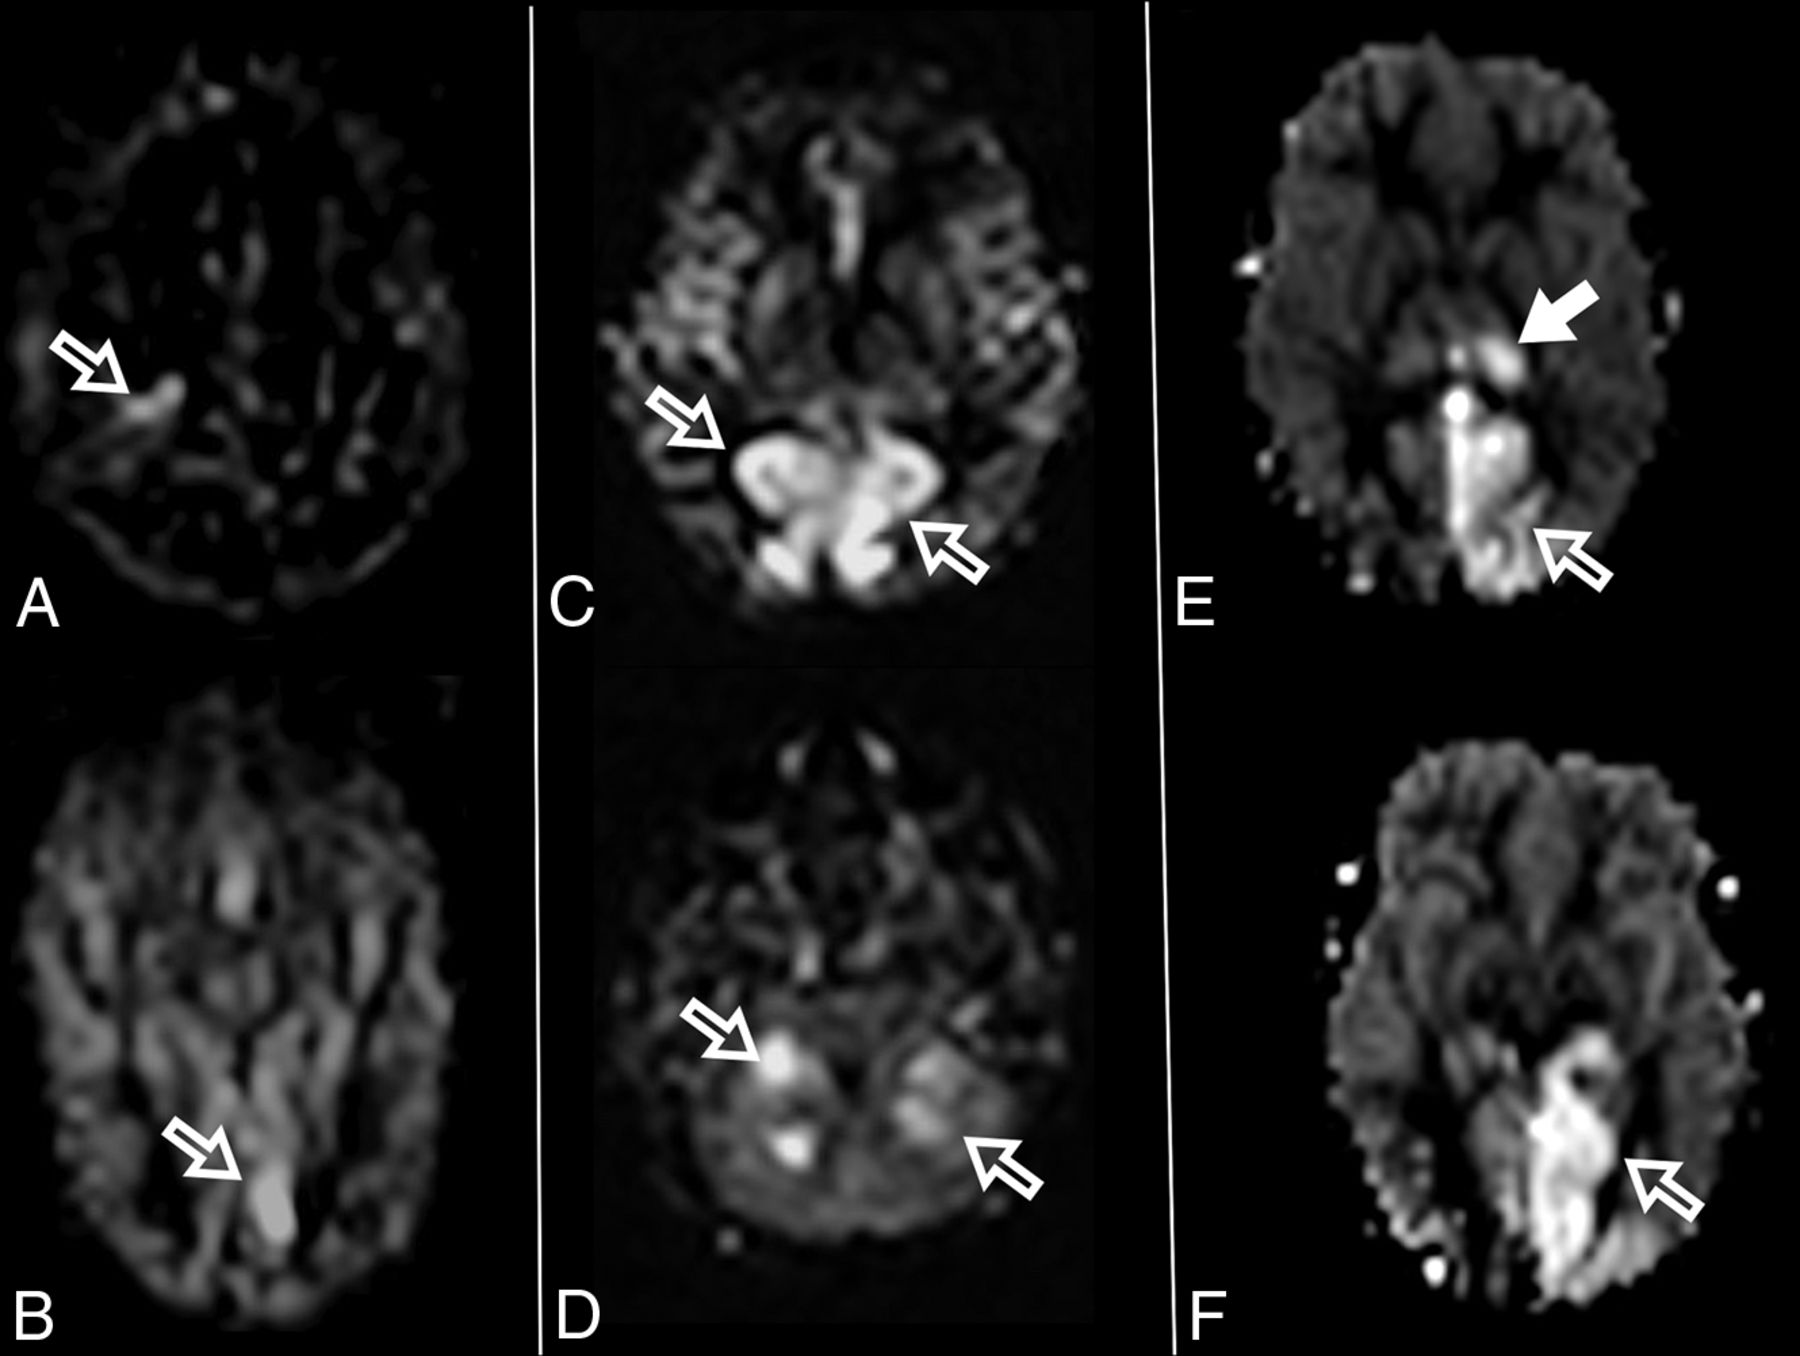

At diagnosis, brain MR imaging findings were abnormal in most patients (n = 12, 92%). The most common brain MR imaging findings were unilateral or bilateral perirolandic signal changes (n = 7, 54%) (Fig 1) and unilateral or bilateral thalamic signal changes (n = 10, 77%) (Fig 2). Perirolandic signal abnormalities were unilateral in most cases (n = 5, 71%) and were more frequently seen only affecting the precentral or both the pre- and postcentral gyri. Half of the thalamic changes were unilateral (n = 5, 50%). Simultaneous perirolandic and thalamic signal changes occurred in 6 patients (n = 6, 46%). An association of EPC (clinically/EEG) and perirolandic signal changes was present in 6 patients (n = 6, 75%), and an association of EPC (clinically/EEG) and thalamic signal changes, in 7 patients (n = 7, 87.5%). Two patients with EPC (clinically/EEG) did not present with perirolandic signal abnormalities. The findings positive for lesions overall were on the DWI of 10 patients (n = 10, 83%), on the T2WI of 9 patients (n = 9, 75%), and on FLAIR of 7 patients (n = 7, 58%). In 4 patients, DWI was the only sequence with abnormal findings. The occipital lobe was affected in the early brain MR imaging in 2 patients (n = 2, 15%). Signal changes in other brain regions were found in 5 patients (n = 5, 42%), involving multiple regions, namely the cerebral white matter, insula, putamen, caudate nucleus, fornix, cerebellar vermis, and also the frontal and occipital lobes. One patient did not present with either perirolandic or thalamic changes but instead presented with a diffuse pattern similar to that of leukoencephalopathy, with restricted diffusion in the white matter and white matter tracts (Fig 3). Three patients had an abnormally high lactate peak on MR spectroscopy. None of our patients had ASL or other perfusion-weighted imaging at the time of diagnosis. T1 and T2* imaging and SWI had negative findings at the time of diagnosis.

Perirolandic sign in 4 different patients with POLG-related disorders (A, An 8-month-old female), (B and C, A 3 year-old-male), (D, An 1-year-old male) and (E and F, A 9-month-old female). Signal changes around the central sulcus were variable with varying degrees of conspicuity. A, T2WI. Signal changes are subtle and focal, evident only in the left precentral gyrus (open arrows). B, T2WI. Signal changes are subtle and focal, evident in the left pre- and postcentral gyrus (open arrows), but more conspicuous in the DWI (open arrows, C). D, DWI. Linear signal changes involving mainly the cortex surrounding the right central sulcus (open arrows). E and F, DWI and ADC map, respectively. Marked signal changes in both right pre- and postcentral gyri.

The MR imaging appearance of the perirolandic sign was varied. Signal changes involved both the pre- and postcentral gyri, more commonly in the precentral gyri. The conspicuity of the perirolandic sign was also variable (Fig 1). In the more notable cases, signal changes were ribbon-like following the course of the gyri, which were readily detectable as T2 hyperintensities and restricted diffusion. DWI was the most sensitive MR imaging sequence to detect signal changes and, therefore, should always be included in the protocol and carefully evaluated when a case of POLG-RD is suspected.